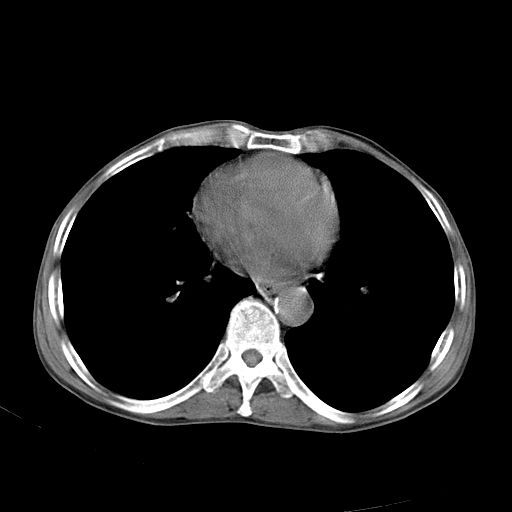

以下是引用苯小孩在2007-5-24 12:47:00的发言:[br]右侧肺门处不均匀密度软组织块影,远端肺组织见斑片模糊影,纵隔内淋巴结明显肿大,边界不清.<纵隔窗第12层面支气管内似见软组织结节>[br]考虑:1、右侧中央性肺癌并阻塞性肺炎并纵隔淋巴结转移可能性大.建议强化或纤支镜进一步检查.[br]2、隆突下淋巴结肿大/食道病变?请做鉴别检查.

以下是引用jw-830在2007-5-24 15:24:00的发言:[br][br] [br] 考虑右肺中央型肺癌并阻塞性炎症,右肺门及纵隔淋巴结转移。 [br] [br][br]